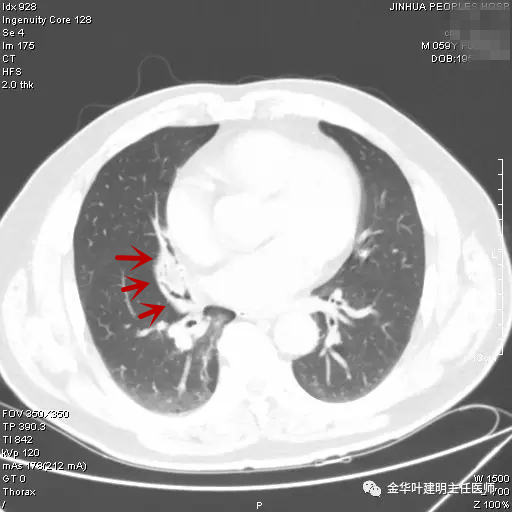

患者陈某,金华人,前一年的11月份因外伤到医院检查胸部CT时,发现右肺中叶异常,以下是CT图片与报告:

胸部CT:右肺中叶及下叶慢性炎症,部分支气管管腔略变窄,建议复查。

图一示:第1次胸部CT时的肺窗